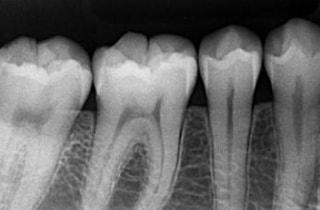

デジタルレントゲン

患者様に負担をかけず、現状を詳しく把握すること。

超高感度だから被曝量が軽減され、お子様にも優しいレントゲン。

当院のデジタルレントゲンは、従来のフィルムを使用したレントゲン撮影に比べ、人体に受ける放射線の量を、約1/4~1/10に抑える事が可能です。

照射時間が短縮され、より低線量でのレントゲン画像取得が可能となります。

お子様にも安心です。